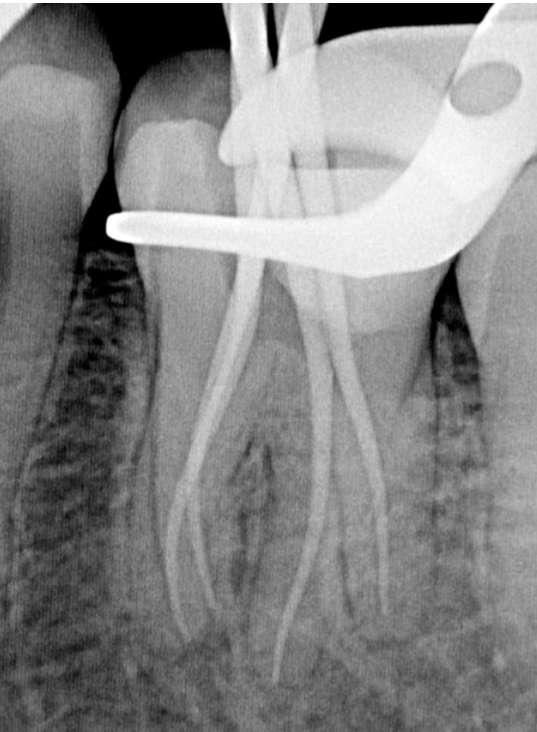

Die endodontische Behandlung fand in einer Sitzung statt. Nach Anästhesie und Anlegen des Kofferdams erfolgte die Entfernung der provisorischen Füllung und die initiale intrakoronale Diagnostik. Mittels Microopener konnte ein mesiobukkaler, mesiolingualer, distobukkaler und distolingualer Wurzelkanal sondiert werden. Die Ausarbeitung der primären Zugangskavität zur besseren Zugänglichkeit der Kanäle erfolgte mit Langschaftrosenbohrern. Anhand des präoperativen diagnostischen Röntgenbilds konnte die Länge der Wurzelkanäle vorläufig näherungsweise bestimmt werden. Die Kanäle wurden im weiteren Therapieverlauf kontinuierlich mit 6% NaOCl gespült. Nach Ausarbeitung der Zugangskavität folgte die koronale Erweiterung der Wurzelkanäle mit EdgeEndo X7 Feilen der Größe 17.06. Die elektrometrische Bestimmung der Kanallänge mithilfe eines Morita Root ZX Mini Apex Locators wurde mit C-Piloten der Größe 8-10 durchgeführt. Nach Festlegung der Arbeitslänge wurde der

Gleitpfad rotierend mit EdgeFile X7 der Größe 17.04 und 25.04 erweitert und final bis auf 30.04 aufbereitet (Abbildung 2).

Abbildung 2: Blick auf das mesiale Kanalsystem nach Präparation